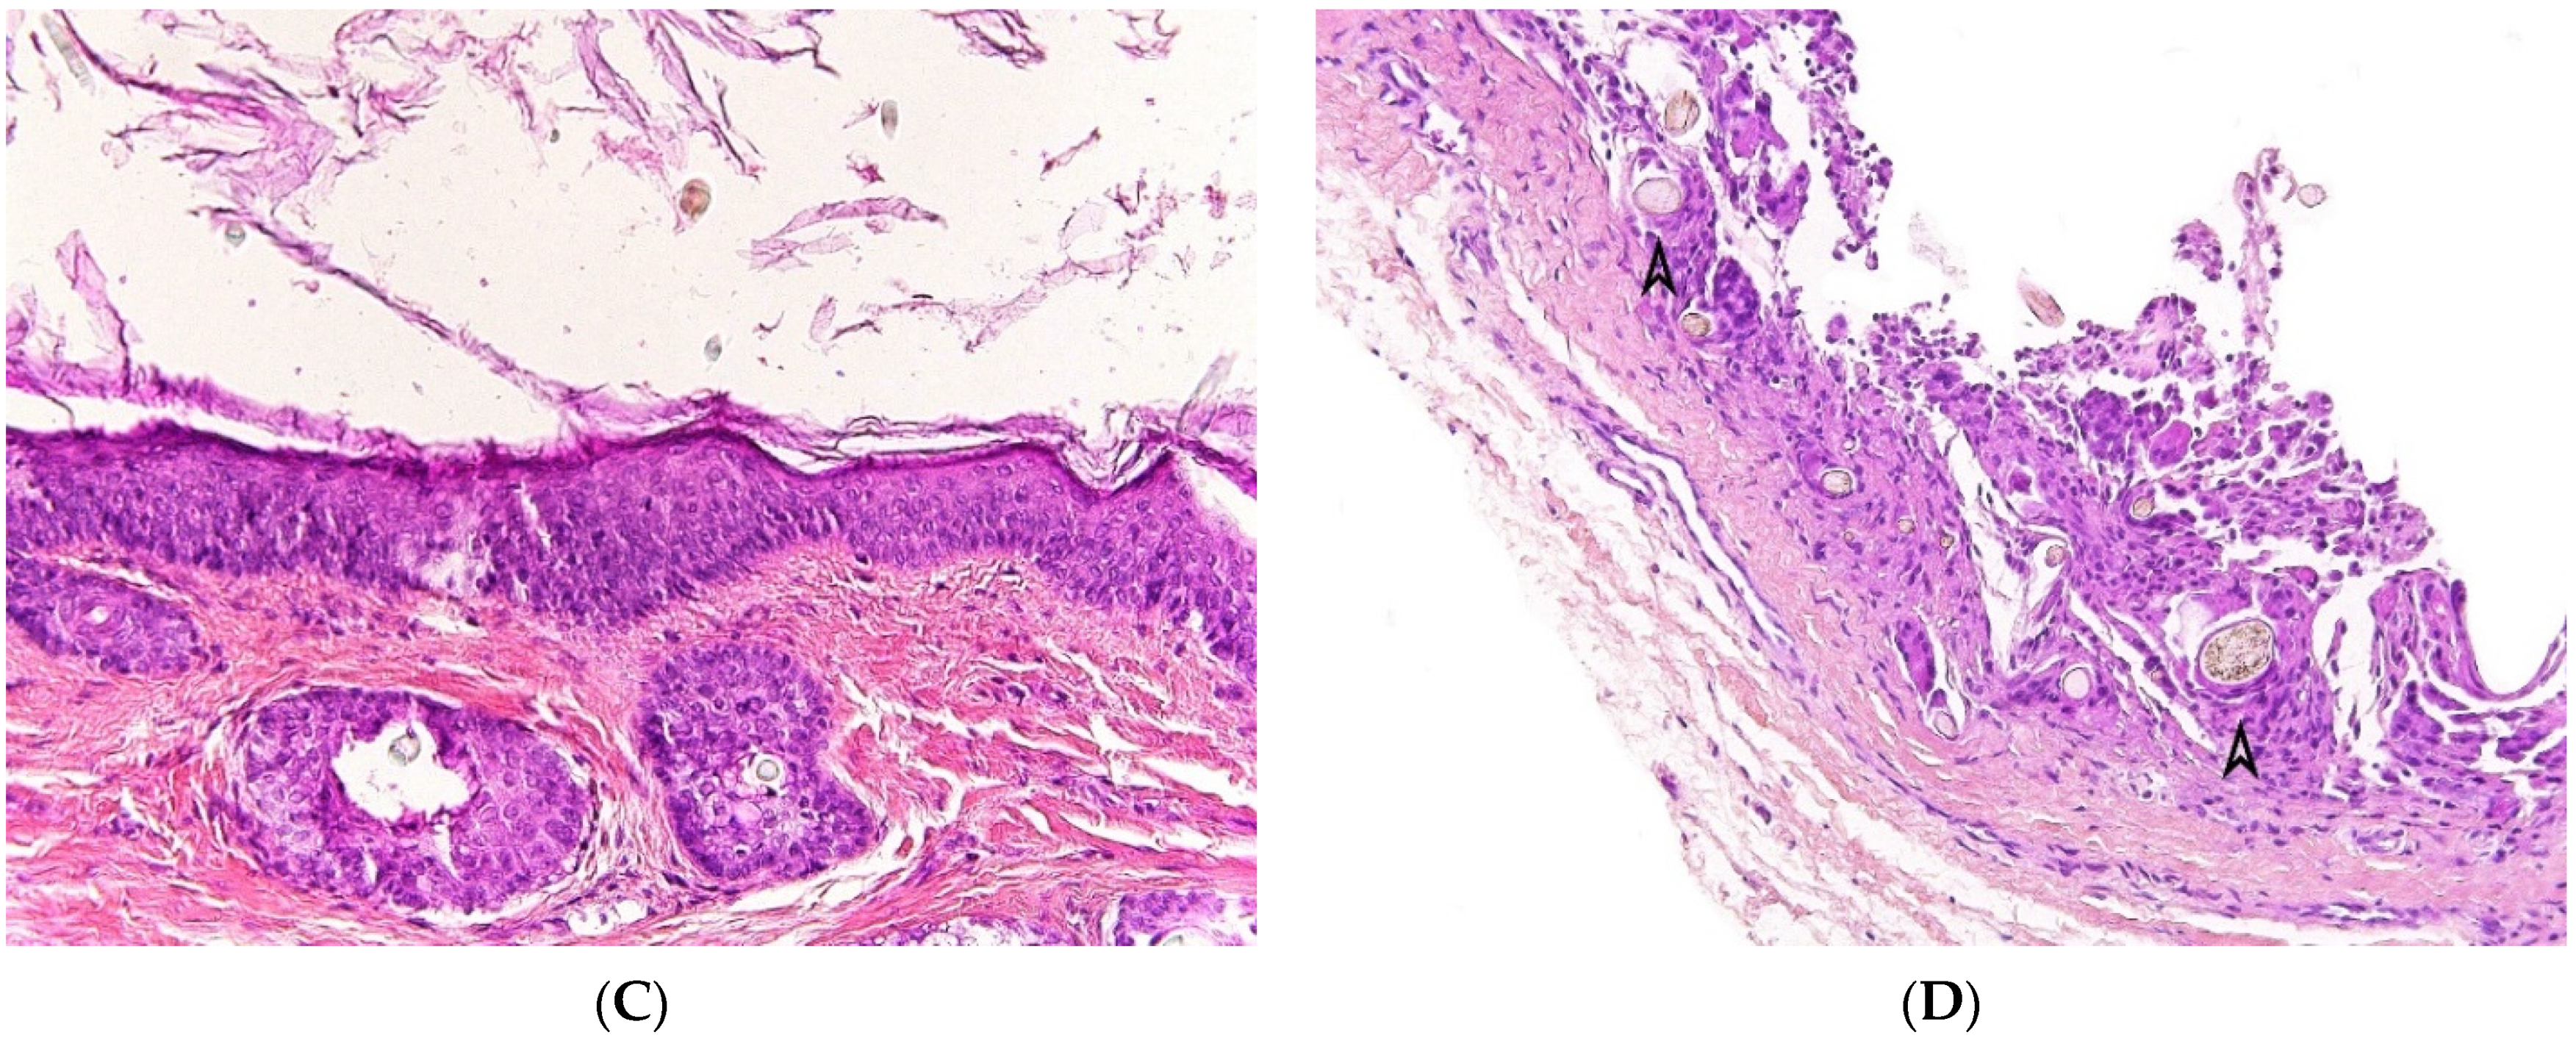

2.6.2. Histopathological Features

The bronchogenic cyst presents itself as an extrapulmonary unilocular cyst. The lumen contains fluid, turbid, mucinous or purulent material. Its wall is lined by respiratory epithelium overlying fibromuscular connective tissue containing seromucinous glands and cartilage plates (Figure 7A,B). Squamous metaplasia may occur. The presence of cartilage tissue is important for establishing the final diagnosis and differentiating between bronchogenic cysts and other cysts of the neck [27,29].

Figure 7.

Bronchogenic cyst. (A), (H.E.S). unilocular cyst lined by respiratory epithelium overlying circular muscular tunic (arrow). (B), (H.E.S.). In the wall, seromucous glands (arrowheads) and cartilage plates (*).